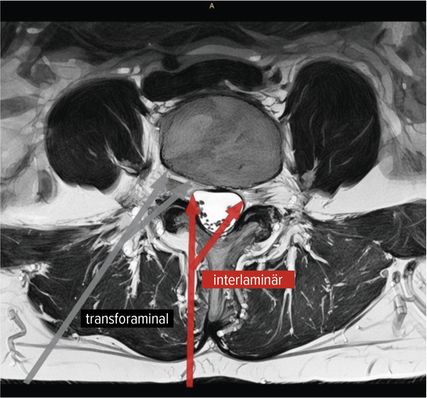

Der interlaminäre endoskopische Zugang bietet Vorteile in den Segmenten L4/5 und L5/S1 aufgrund der Weite des Interlaminärfensters. Dem Chirurgen kommen dabei die Erfahrungen des offenen interlaminären Zugangs zugute, da die Ausrichtung des Sichtfeldes und anatomische Orientierung ident sind. Während der transforaminäre Zugang vorwiegend bei Diskektomien zum Einsatz kommt, hat die Entwicklung des IL-Zugangs das Indikationsspektrum erweitert. Zentrale Spinalkanalstenosen, Rezessusstenosen, aber auch die kontralaterale Foraminotomie sind mögliche Einsatzgebiete.11–13Abbildung 2 illustriert die interlaminäre (roter Pfeil) und transforaminäre (grauer Pfeil) endoskopische lumbale Zugangstrajektorien (MRI-t2-gewichtet). Abbildung 3 zeigt das Kambin-Dreieck. Dieses weist die Form eines rechtwinkligen Dreiecks auf und wird durch die austretende Nervenwurzel (Hypotenuse), den Duralsack, den Processus articularis superior des Facettengelenkes und die Grundplatte (Basis) begrenzt. Es stellt eine sichere Landungszone für das Endoskop im Neuroforamen dar.